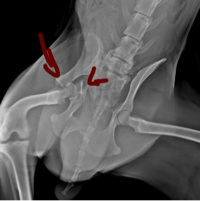

O Amarelinho sofreu uma fratura grave, uma fratura muito feia, como mostra o raio-X.

Ele sente muita dor e depende totalmente da nossa ajuda para ter uma chance de voltar a andar.

👉 A única chance do Amarelinho é uma cirurgia ortopédica, no valor de R$ 3.500,00.

Sem essa cirurgia, ele pode não voltar a andar e ficar com sequelas permanentes.